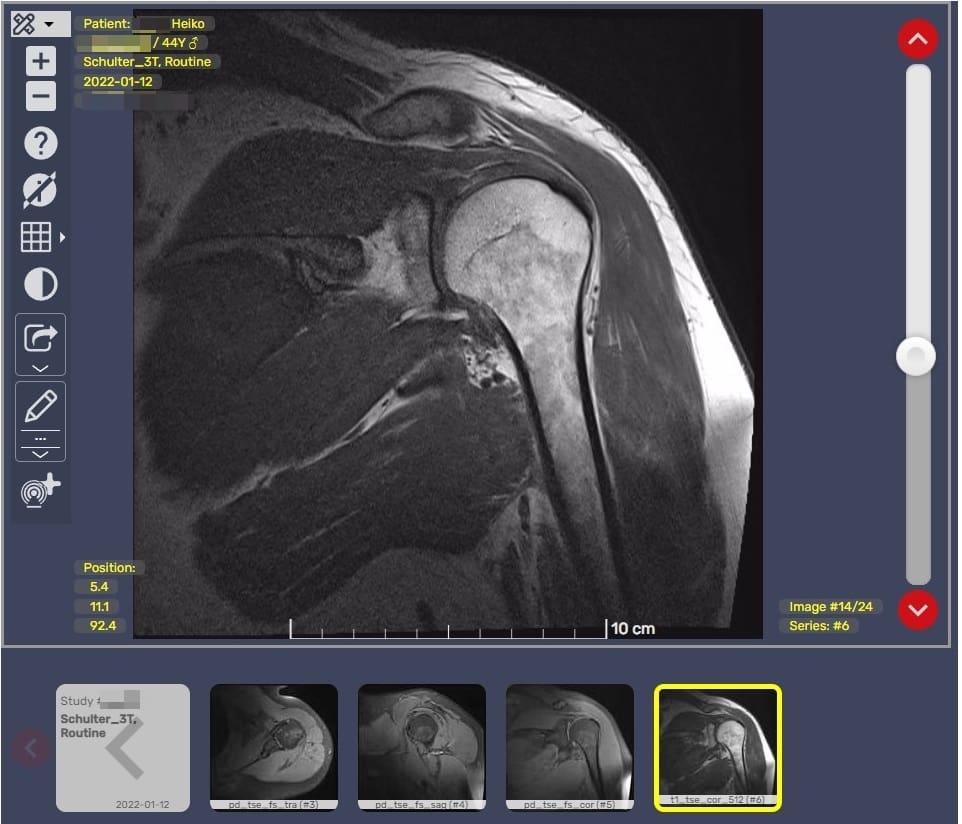

Nach 10 Minuten war das Ganze vorbei. Dann bekam ich eine CD und einen Barcode um mir dies Online anzuschauen.

Davon war ich begeistert. Auch wenn ich nicht viel davon verstehe, ich konnte mir meine Fettschichten selbst durchschauen 🙂 Cooles Ding.